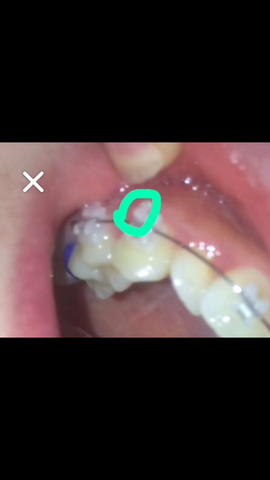

Braces Girlswithbraces Herbst Herbstappliance Zahnspange Zahne Mund

Ist Meine Zahnspange In Ordnung Gesundheit Und Medizin Gesundheit Arzt

Warum Habe Ich Keine Brikett Gummis Und Nur Diese Elastics Arzt Zahnarzt Zahnspange